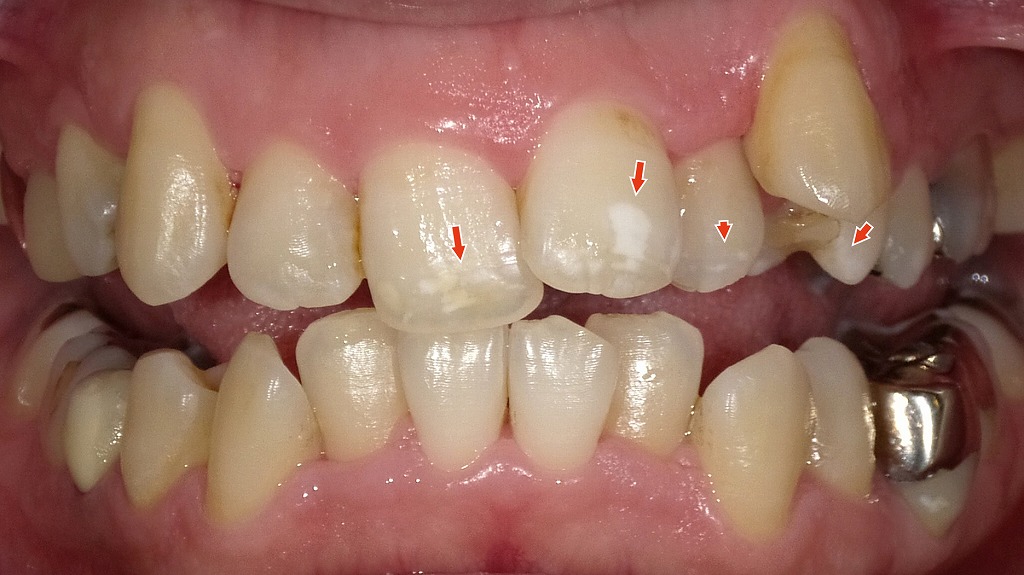

ホワイトニングでホワイトスポットが僅かに改善した症例

1枚目の画像:術前

1枚目の画像では、エナメル質形成不全によるホワイトスポットが確認できます。特に左上の中切歯(前歯の中央右側)に明瞭な白濁が見られ、隣接する側切歯や犬歯にも白い不透明な部分が点在しています。

2枚目の画像:ホワイトニング後

2枚目の画像では、ホワイトニング処置後の状態です。歯全体の色調がやや明るくなり、周囲とのコントラストが緩和されたことで、ホワイトスポットがわずかに改善し、以前より目立たなくなっています。完全に消失したわけではありませんが、自然な色のなじみが得られています。